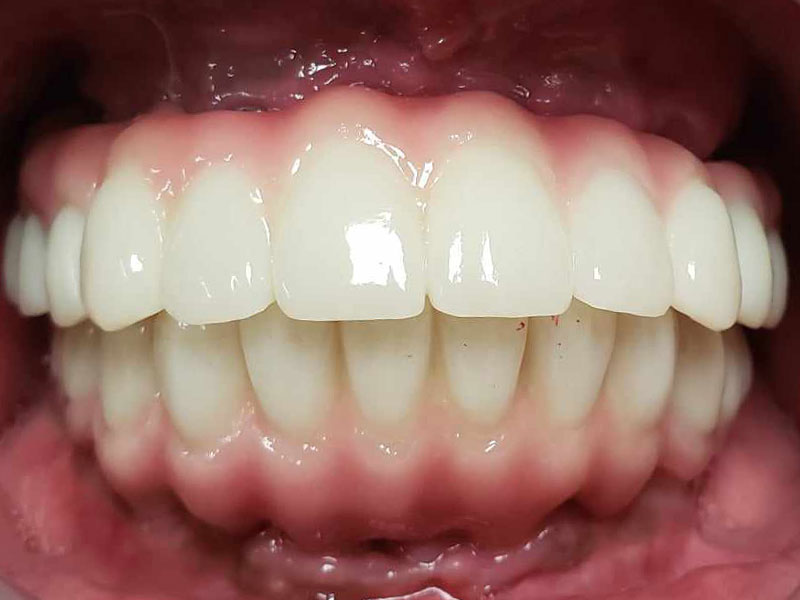

治療後

- 2か月後、抜歯穴の状態が落ち着いてから、最終補綴の型、高さの検査を行い、ねじ止め式の上部構造(チタンフレーム使用+ジルコニア+ガムセラミック)をセット。